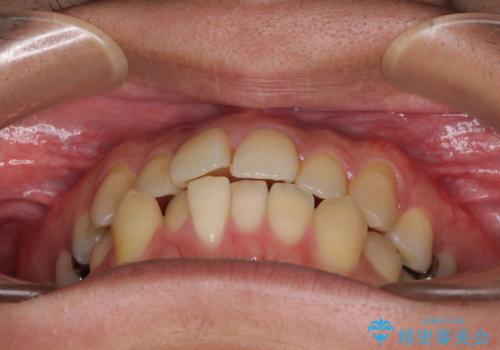

前歯のクロスバイトをインビザラインで矯正治療

- 前歯のデコボコとクロスバイトを気にして来院された患者様です。

前歯を早く整えたいとの希望があったので、ワイヤー矯正にて短期間でクロスバイトを解消し、その後インビザラインにて整えることとしました。